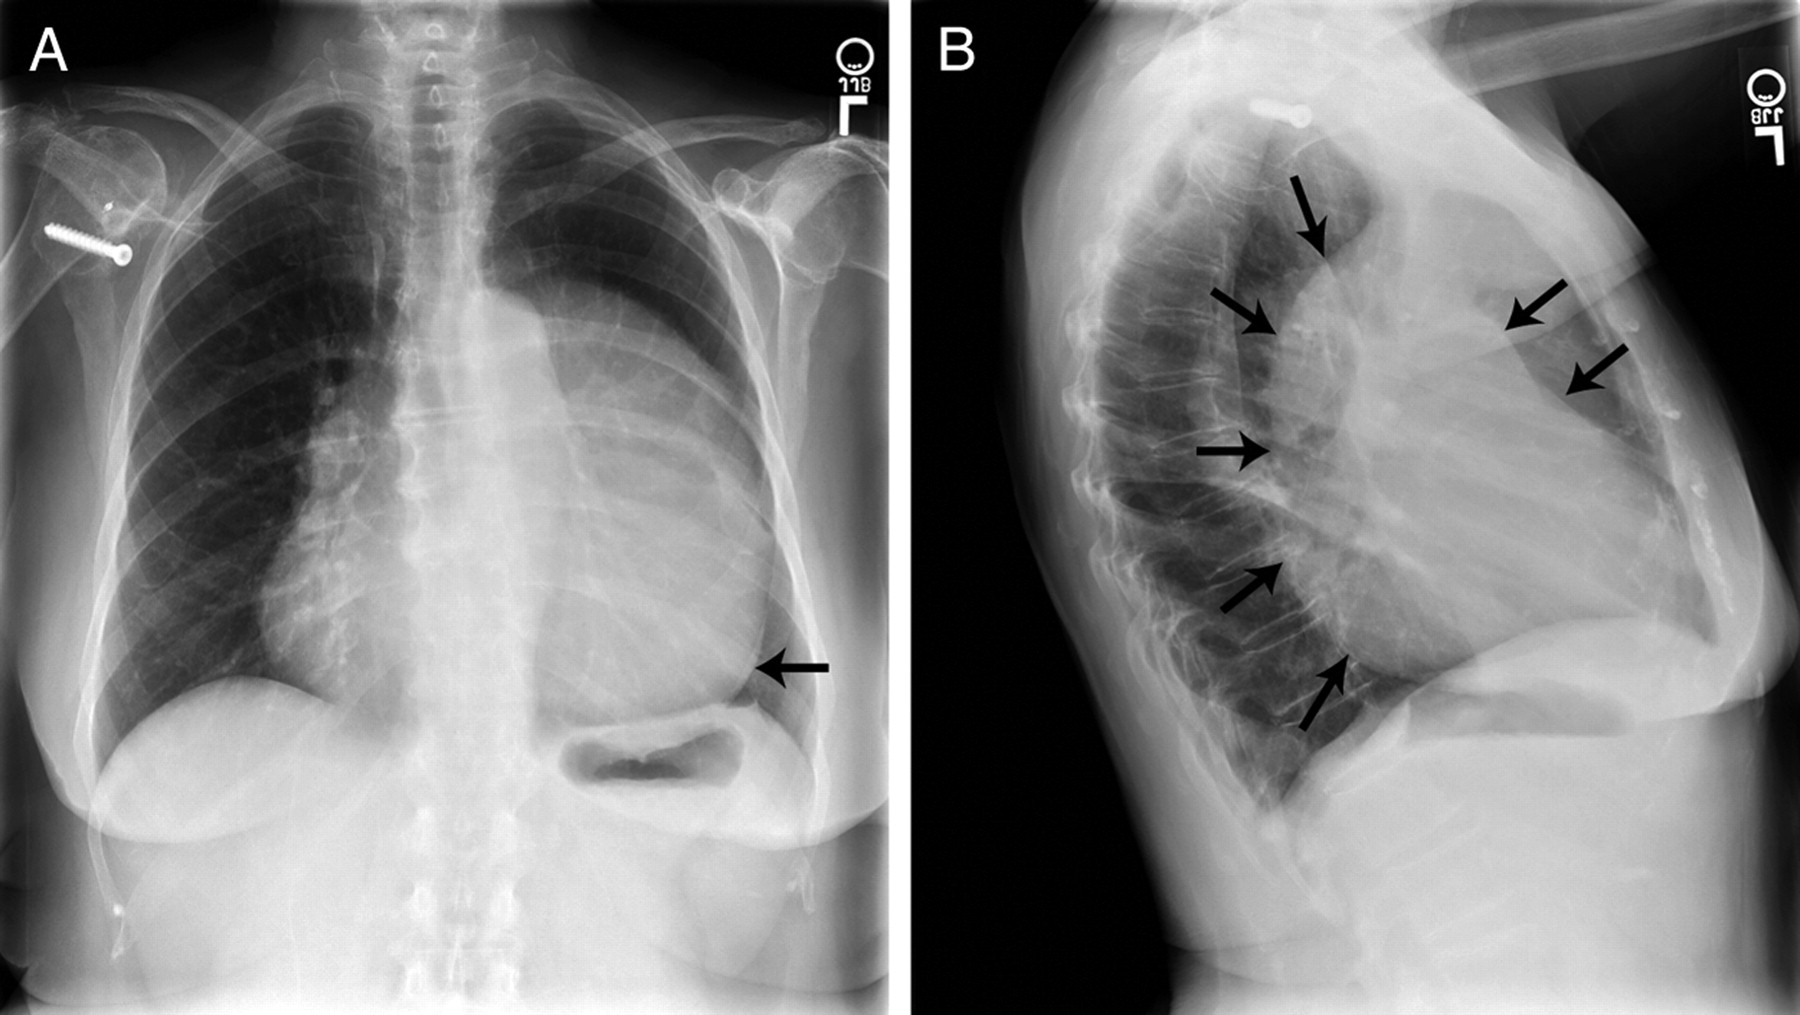

CXR

• Left CPA heart can shift posterior and left causing straightening and elongation of heart (levorotation and levoposition)

• "Snoopy" Sign

ECHO

• Complete CPA better imaged supine give heart shift posterior and leftward

• Exaggerated movement of heart in chest

• Outward bulging of LV inferior wall seen best on 2 Chamber (tear drop shape)

• Need further imaging to confirm

• CMR gold standard